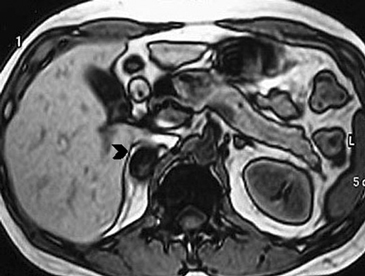

Figura 23. Carcinoma suprarrenal derecho. Corte axial de resonancia magnética ponderado en T2 con saturación grasa (a) en que se demuestra una masa suprarrenal derecha con áreas hiperintensas en su espesor probablemente determinadas por necrosis (flecha) y corte coronal en secuencia TRUFISP (b) en que se observa un trombo tumoral que expande el lumen de la vena cava inferior (cabeza de flecha).Puede también presentar invasión directa de otras estructuras vecinas, como riñón, páncreas, bazo y diafragma.

En RM15 estas lesiones presentan intensidad de señal variable tanto en secuencias ponderadas en T1 como T2, dependiendo de la presencia de componentes necróticos y hemorrágicos, que como ya se mencionó es un hallazgo frecuente. Las áreas de necrosis suelen aparecer hipointensas en T1 e hiperintensas en T2, y las áreas de hemorragia si es en fase subaguda, vale decir aproximadamente una a siete semanas, se observara hiperintensidad de la lesión tanto en secuencia T1 y T2. En fase crónica (a partir de las 7 semanas en adelante) producto del deposito de hemosiderina y la presencia de una capsula fibrosa, las imágenes demuestran un anillo hipointenso tanto en secuencias T1 como T2. Con la administración de gadolinio ev se observa refuerzo de las porciones viables de tumor, con lo que se intensifica la señal.